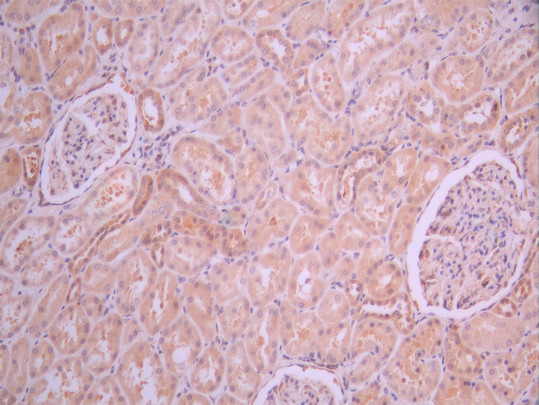

IHC image of CSB-RA310122A0HU diluted at 1:100 and staining in paraffin-embedded human kidney tissue performed on a Leica BondTM system. After dewaxing and hydration, antigen retrieval was mediated by high pressure in a citrate buffer (pH 6.0). Section was blocked with 10% normal goat serum 30min at RT. Then primary antibody (1% BSA) was incubated at 4°C overnight. The primary is detected by a Goat anti-rabbit polymer IgG labeled by HRP and visualized using 0.05% DAB.